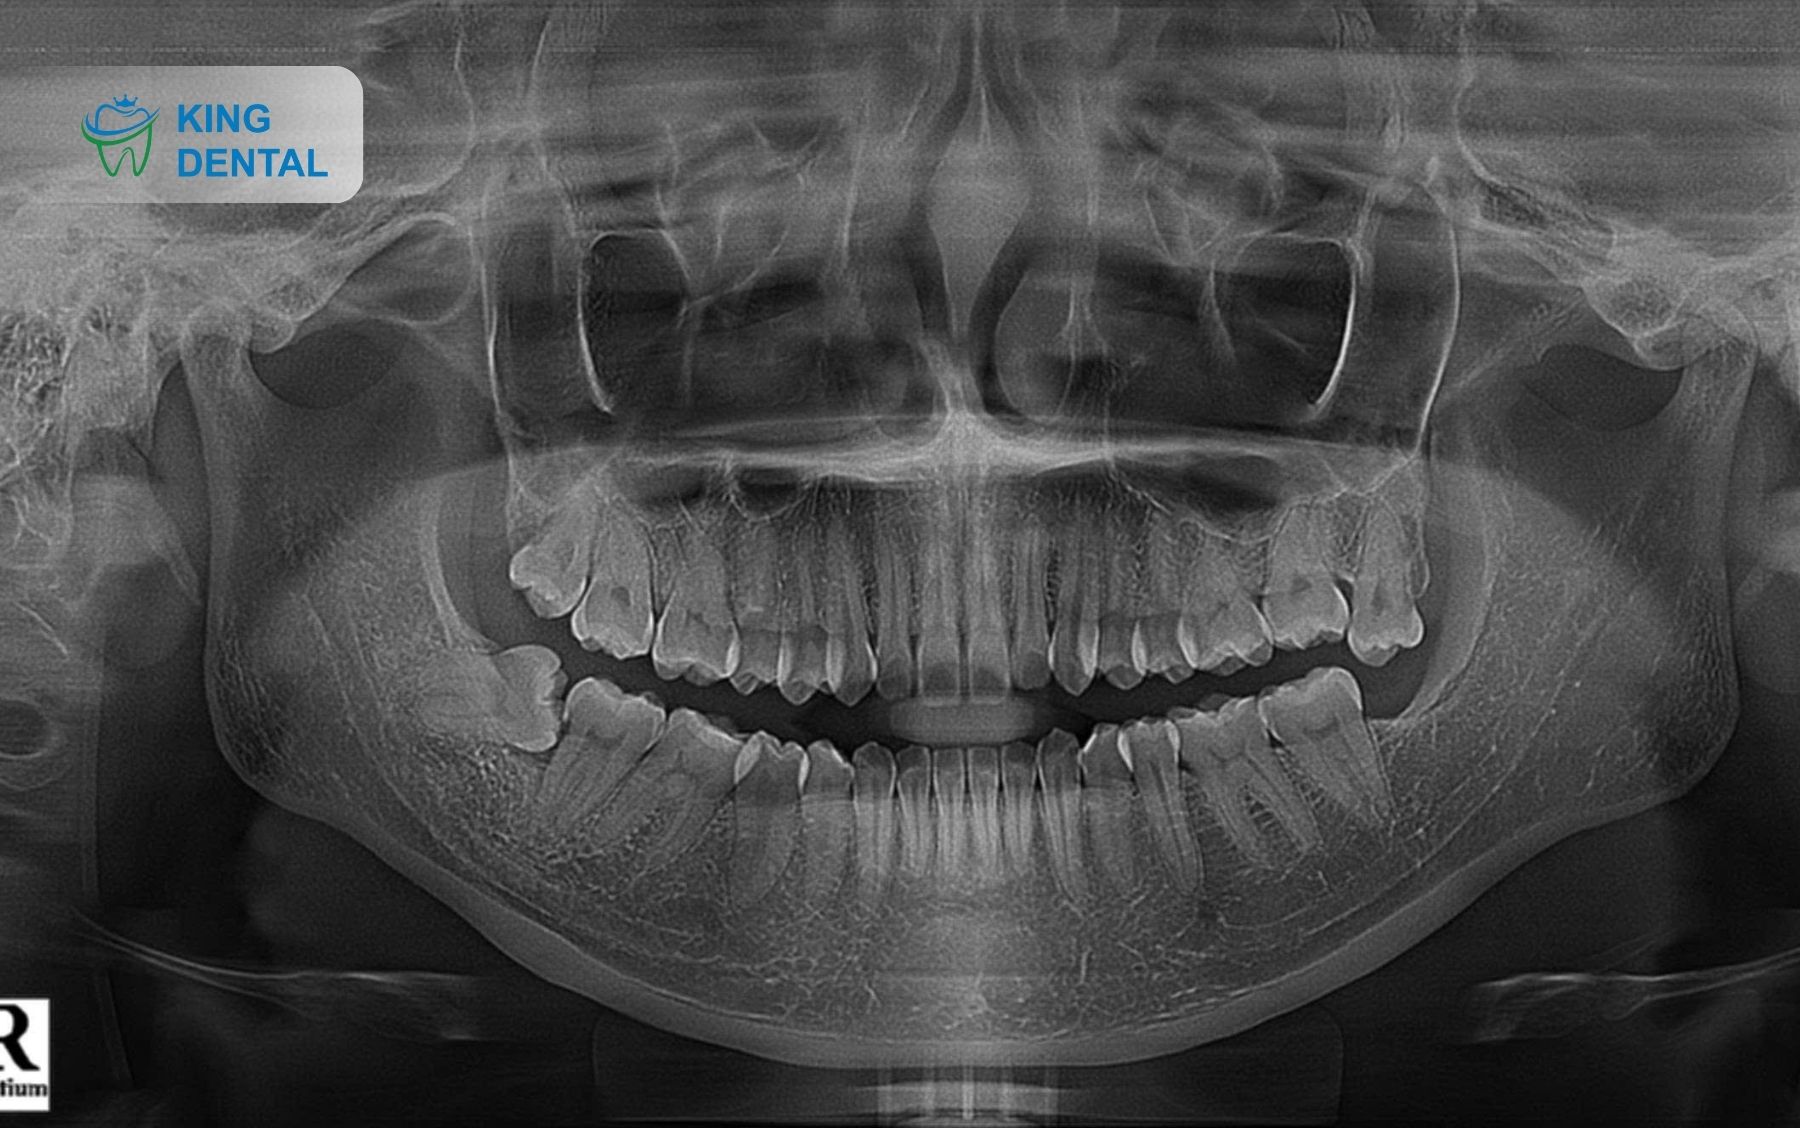

• Chụp X-quang / CT Cone-Beam để xác định chính xác vị trí, hướng mọc và mối liên quan với răng khác, dây thần kinh, xương hàm.

Chụp X-quang răng khôn